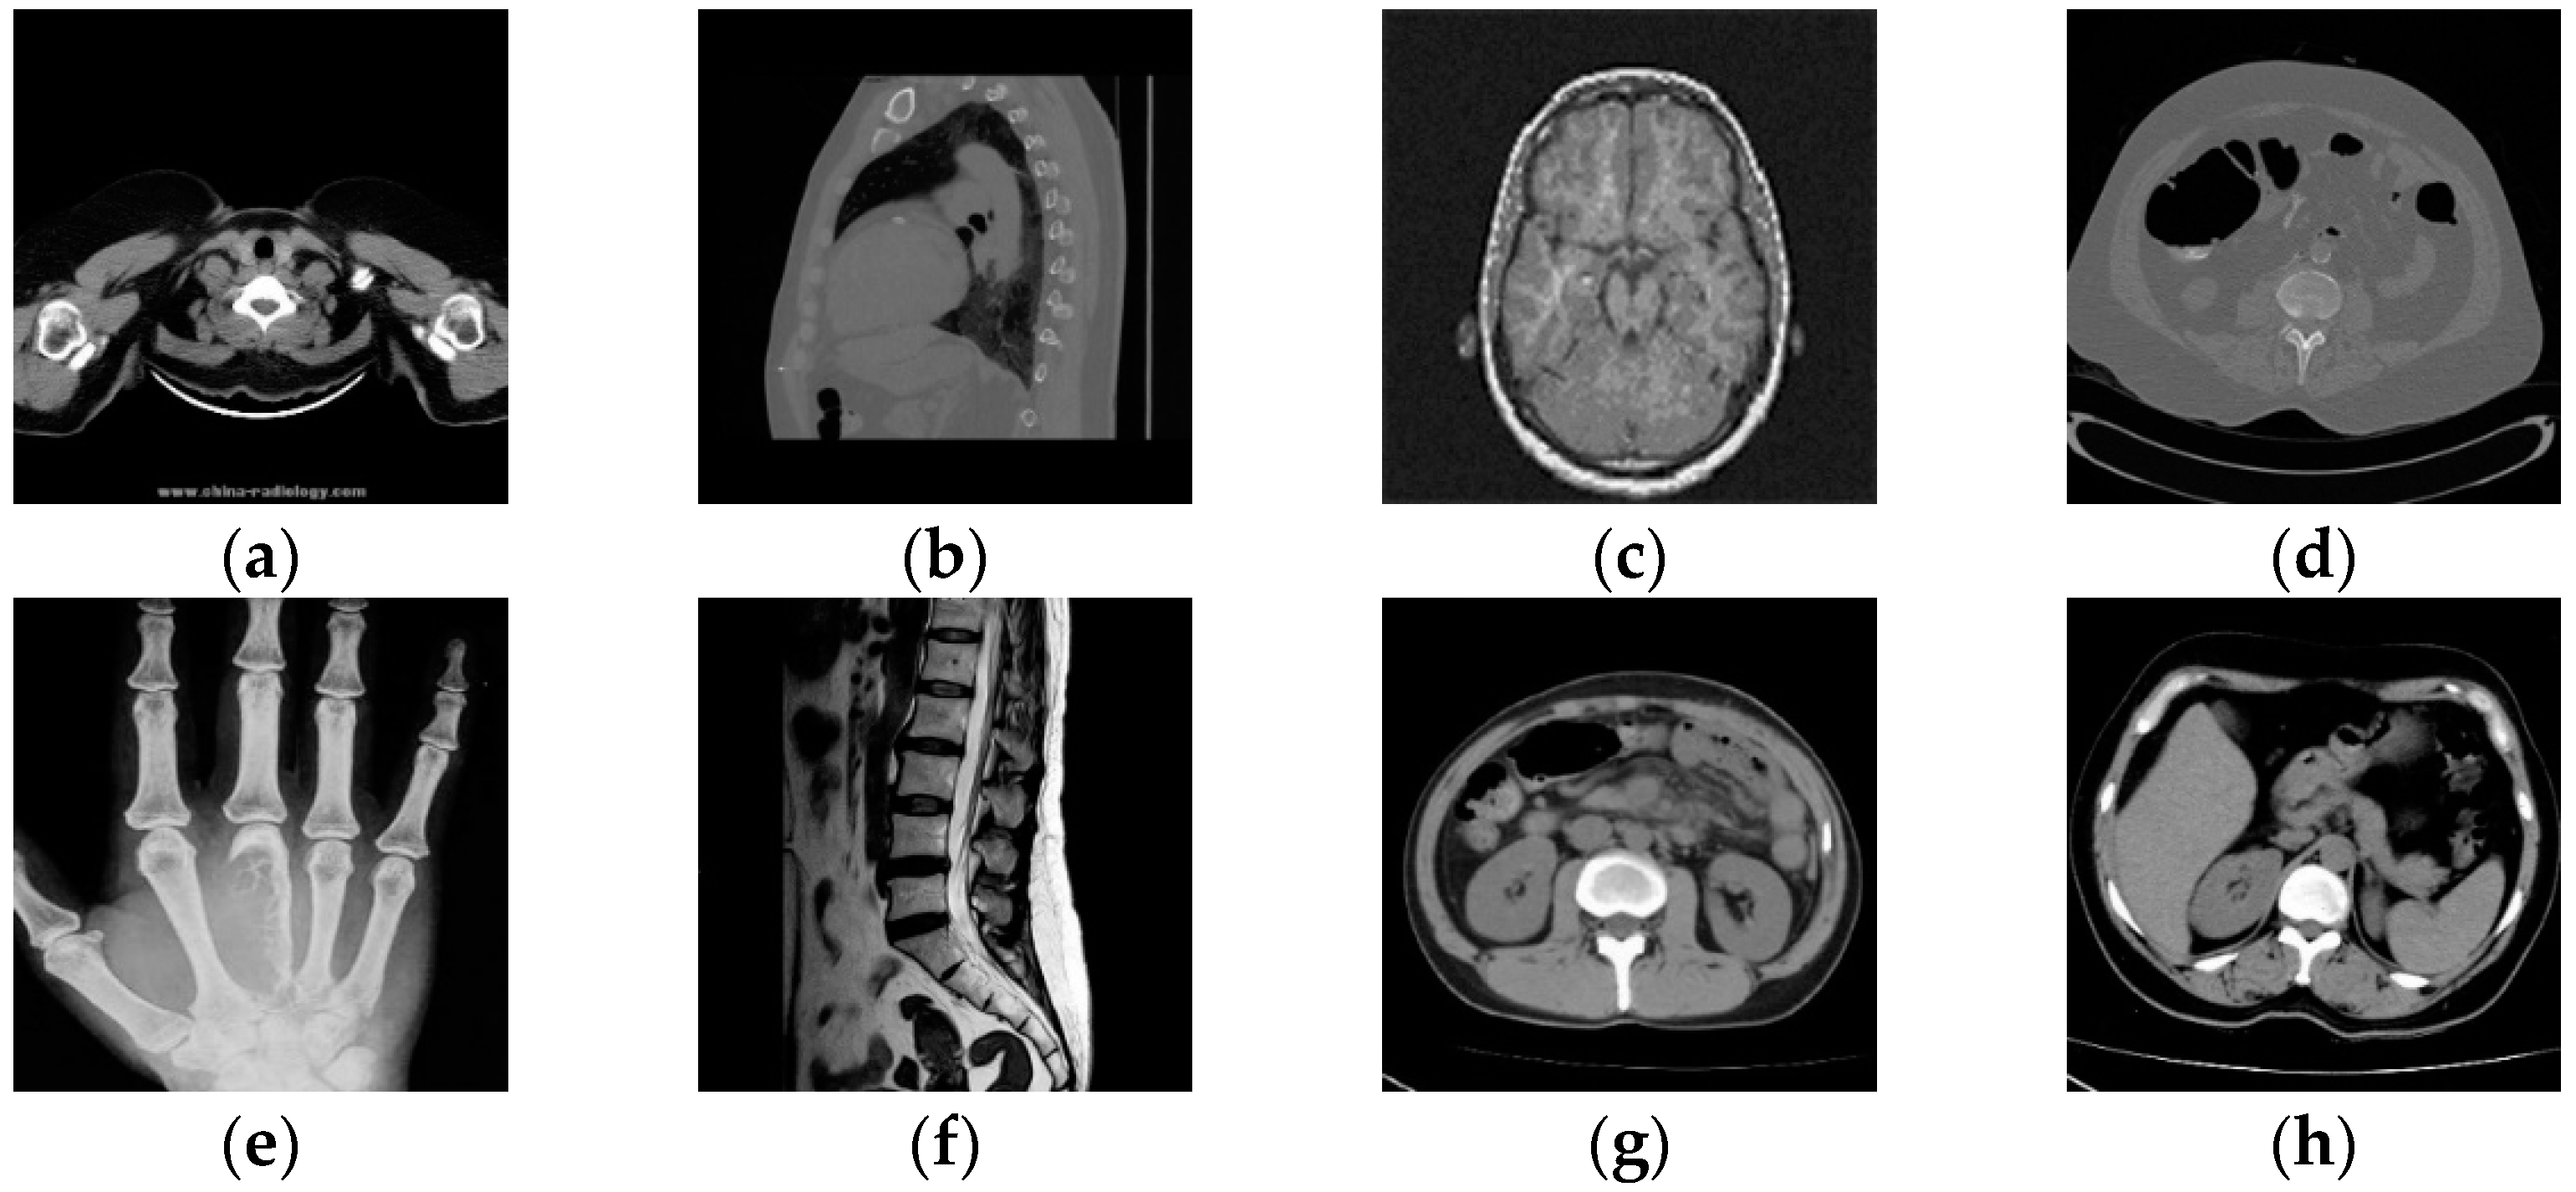

4.2. Reliability Analysis

In order to prove that the deep-learning algorithm proposed in this paper has certain reliability, eight medical images were randomly selected from the test set for testing, as shown in Figure 12. The NC is used to calculate the correlation between different images, and when the NC < 0.5, it indicates that the correlation between different image feature vectors is low, and the feature vectors extracted by this algorithm are representative. Table 2 shows the NC values between eight different cryptographic medical images. Since the absolute values of NC values of different images are less than 0.5 and the NC value of the same image is 1, the algorithm can distinguish different encrypted medical images and is reliable.

Figure 12.

Different medical images within the test (a–h), related encrypted images (i–p).

Table 2.

NC between different encrypted images.